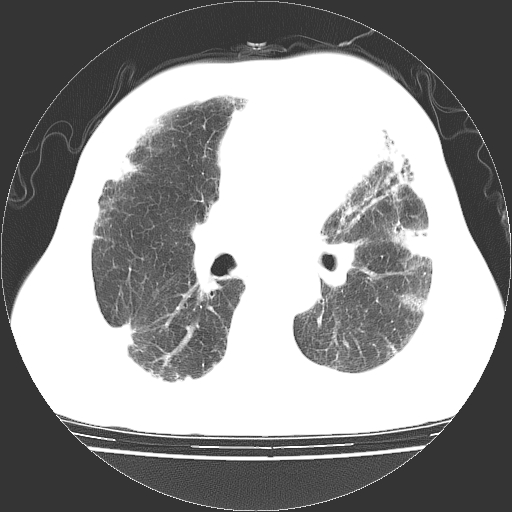

标题: CT25149:男,69岁,反复咳嗽、咳痰五年余,呼吸困难三天。 [打印本页]

男,69岁,反复咳嗽、咳痰五年余,呼吸困难三天。

慢支伴感染、肺气肿、肺心病

慢支伴感染、肺气肿、肺心病!支持!另:间质纤维化!

两肺间质性炎症并感染,左上叶肉芽肿

考虑慢性间质性肺炎并肺间质纤维化。

慢支伴感染、肺气肿、肺心病。双肺间质性改变(间质纤维化)。